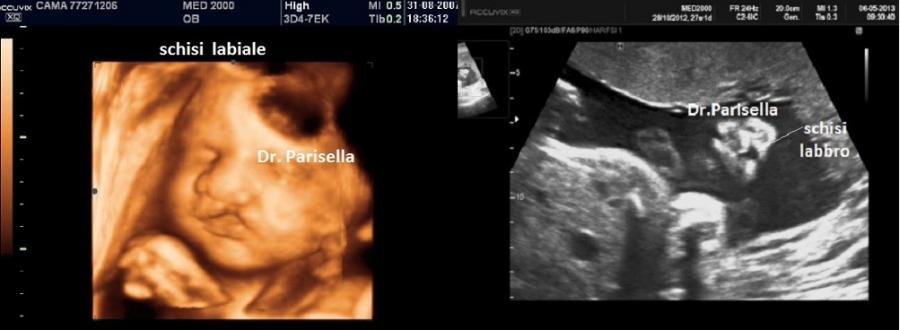

Le lesioni caratteristiche a carico del SNC sono rappresentate  da idrocefalo grave, con ventricoli aperti nello spazio subaracnoideo, ipoplasia cerebrale, anomalie della linea mediana e del setto pellucido (agenesia del corpo calloso); possono essere presenti encefalocele occipitale, una caratteristica conformazione del forame magno “key-hole shaped”, mandibola piccola e naso malformato, labio-palatoschisi. Caratteristica è la polidattilia postassiale alle mani e preassiale ai piedi (l'alluce duplice è altamente caratteristico, quasi esclusivo, di questa condizione morbosa). Segnalati anche piede torto e difetti cardiovascolari (difetti del setto atriale; atrio unico). Come ha segnalato lo studio di Salonen e coll. (1981) condotto su 28 neonati di 18 famiglie, l'esito abituale della gravidanza è la nascita di feto morto o morte in epoca neonatale.

La Diagnosi Prenatale si basa su: 1) assenza di movimenti attivi fetali; 2) polidattilia postassiale alle mani; 3) polidattilia preassiale ai piedi;  4) idrocefalia; 5) polidramnios.